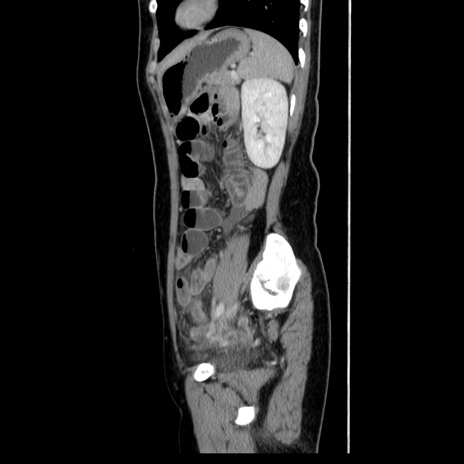

症例39(矢状断像)

【症例】40歳代女性

【主訴】上下腹部痛

【現病歴】2日目から下腹部痛あり。夜間は痛みで眠れなかった。昨日より上腹部痛と下痢が出現。臥位で痛みは軽快したため、休んでいた。本日になって臥位でも立位でも痛みが強くなってきたため救急要請。

【既往歴】子宮内膜症

【身体所見】部:平坦・軟、左上下腹部に圧痛あり、反跳痛あり。

【データ】WBC 21800、CRP 26.78

CT